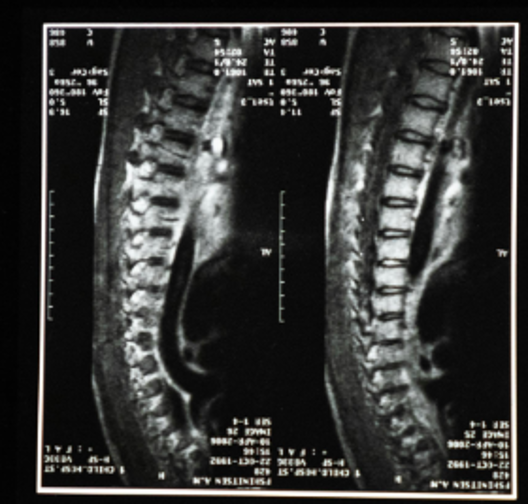

spine imaging

Yet, even the American Academy of Family Physicians recommends against radiologic imaging for low back pain (the fifth most common reason for all physician visits) within the first six weeks. The AAFP cautions away from a structural look even when injury prompted the symptoms, unless very specific red flag neurological deficits are present. Therefore, traditional practitioners acknowledge that imaging doesn’t improve outcomes, just costs! However, I know from my prior decade as a neuroplasticity-naive Family Physician, the tendency to ignore this recommendation for a demanding patient.

What few physicians fully understand is that 85% of chronic low back pain cases involve no evidence of abnormality in the back itself [Deyo et al, 1992]. Conversely, patients without symptoms (asymptomatic) of back or neck pain commonly have the findings you see in the chart above [Brinjikji et al, 2015]. Even scoliosis and kyphosis (hunchback) don’t necessarily cause pain. Therefore, we can’t link age-related wear-and-tear findings with pain.‍ ‍